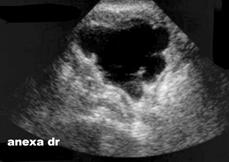

Chistadenom seros drept confirmat

anatomopatologic: imagine sagitala mediana 1, anexa dreapta 2-4.

Diagnosticul diferential se face cu chist ovarian exofitic, neoplasm

chistic, chist paraovarian.